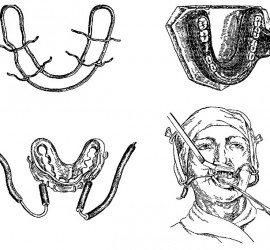

Цемент поликарбоксилатный (ТУ 64-2-275-78) выпускается Харьковским производственным объединением «Стома» (Украина). Предназначен для пломбирования молочных зубов и временных пломб, в качестве прокладок под постоянные пломбы из амальгамы, пластмассы и силикатного цемента, а также для фиксации вкладок, различных видов коронок, небольших мостовидных протезов и ортодонтических аппаратов. Поликарбоксилатный цемент выпускается в виде комплекта […]